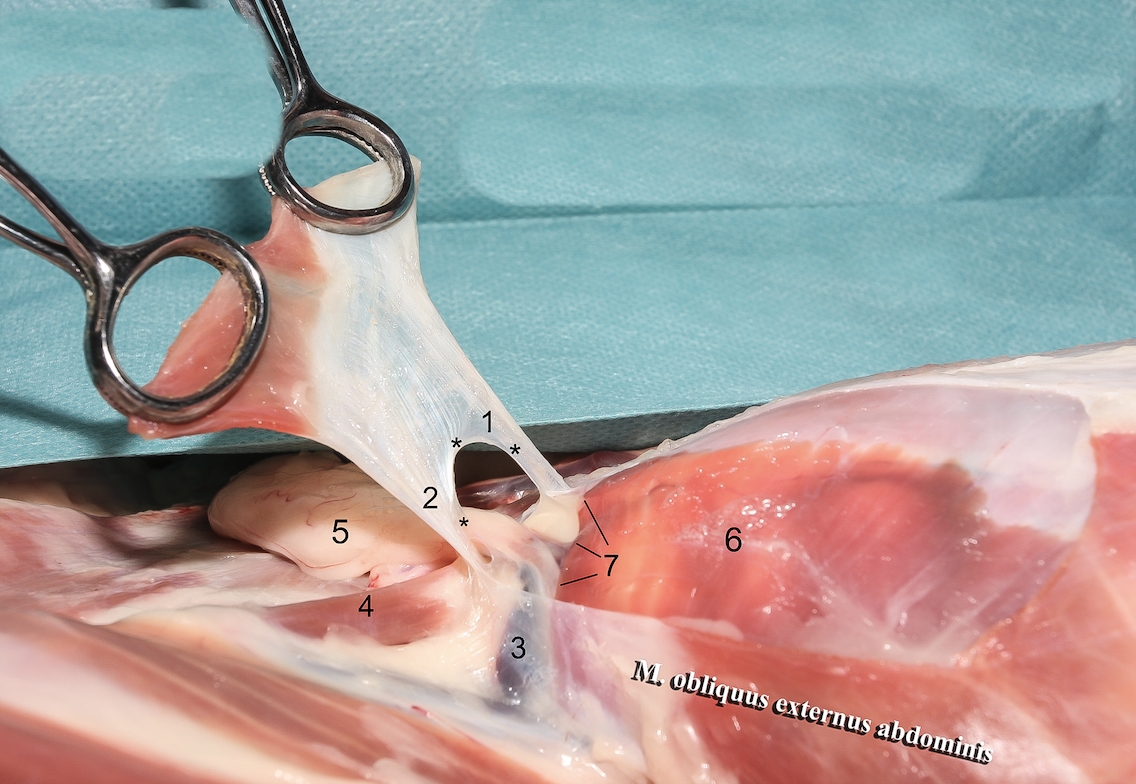

**Anulus inguinalis superficialis**

26

**M. obliquus internus abdominis**

27

**M. obliquus externus abdominis**

28

**Tunica vaginalis**

29

**Proc. vaginalis**

30

**Lig. teres uteri**